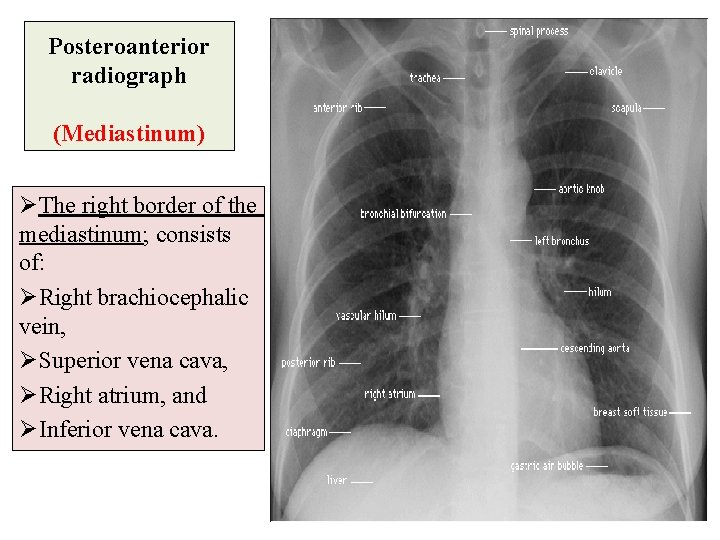

Posteroanterior radiograph (Mediastinum) ØThe right border of the mediastinum; consists of: ØRight brachiocephalic vein, ØSuperior vena cava, ØRight atrium, and ØInferior vena cava.